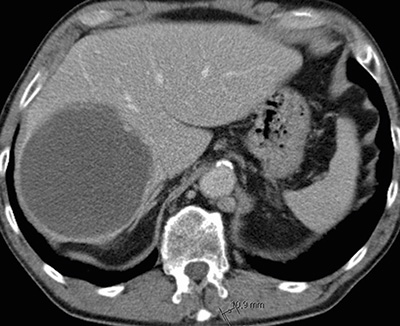

Figur 3. Karcinoidmetastas i levern. Delvis nekrotisk metastas före SIRT (selektiv intern radioterapi) (övre bilden). Oförändrad storlek av nekrotisk metastas 2 år efter SIRT-behandling (undre bilden).